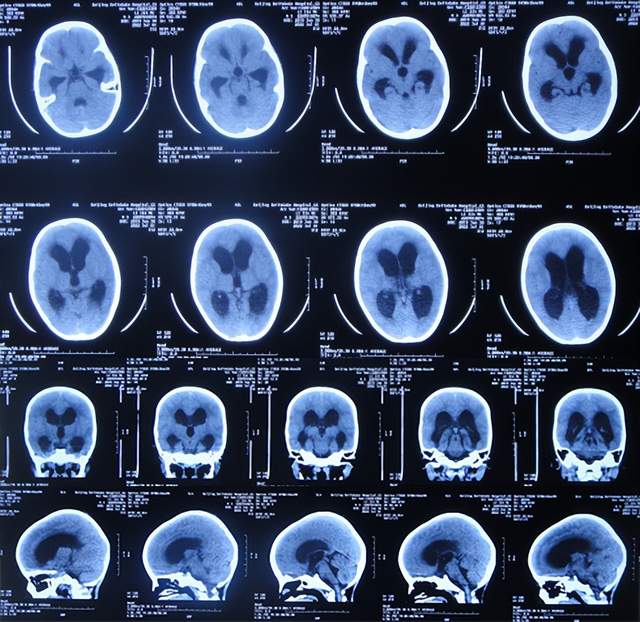

入院当天查头颅CT示脑室扩张(图-8)。

图-8:2022年7月1日入院时头颅CT

住院治疗18天即2022年7月18日,查头颅CT示脑室有缩小(图-12)。

图-12:2022年7月18日头颅CT

住院治疗63天即2022年9月1日,常规查头颅CT示脑室引流术后状态(图-15)。

图-15:2022年9月1日头颅CT

2022年10月12日(住院治疗104天),已夹闭脑室引流管3天,查头颅CT示脑室未见异常(图-17)。

图-17:2022年10月12日头颅CT

2022年10月19日(住院治疗111天),拔除了脑室引流术,拔管前和拔管后头颅CT(图-18)对比。

图-18:2022年10月19日拔管前后头颅CT对比

2022年10月25日(李小勇脑脊液科治疗117天),出院时:精神状态挺好,大小便正常,虽右腿走路稍差但走路速度变快,变稳(图-19);出院时头颅CT示未见异常(图-20)。

图-20:出院时头颅CT